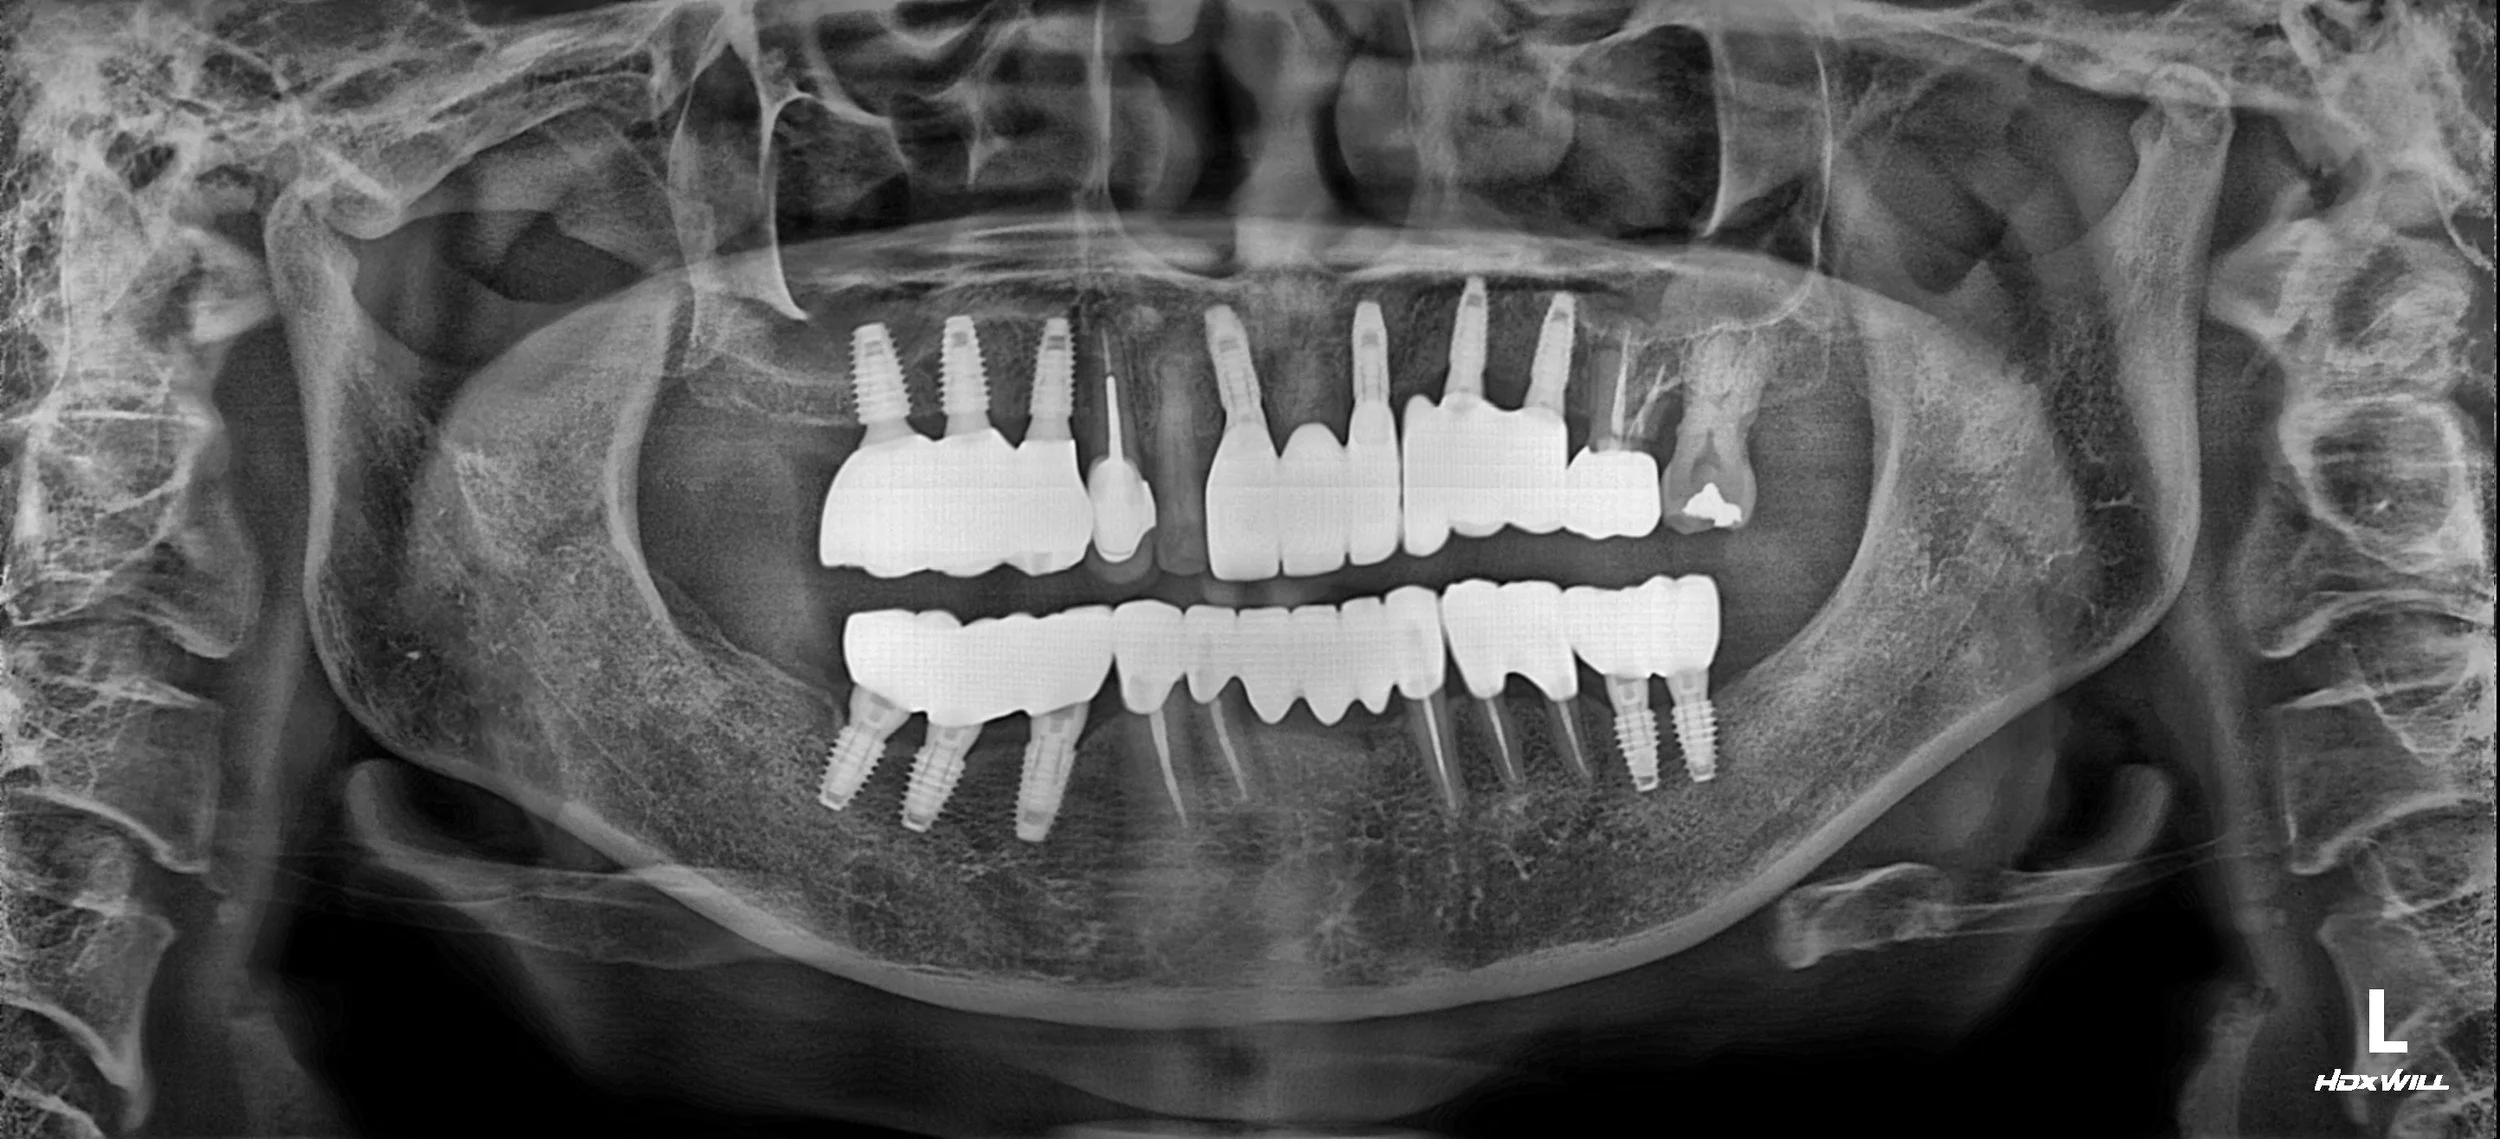

INTRA ORAL - AFTER

1. Periodontal & Surgical Phase: Removal of non-restorable teeth followed by comprehensive periodontal therapy. Dental implants were strategically placed in both the anterior and posterior segments. Extensive guided bone regeneration (GBR) was required in areas of severe atrophy to ensure a stable foundation.

2. VDO Management: The patient’s vertical dimension was systematically elevated using long-term provisional restorations. This phase was crucial for assessing the patient's neuromuscular adaptation to the new bite height and refining the final occlusal plane.

3. Prosthetic Reconstruction: Once stability was confirmed, definitive zirconia implant-supported bridges and crowns were delivered. Particular attention was paid to the "emergence profile" and crown contouring to ensure the patient could easily perform oral hygiene.

The patient successfully transitioned from the discomfort of failing dentures to the security of a fixed, functional, and aesthetically pleasing dentition.